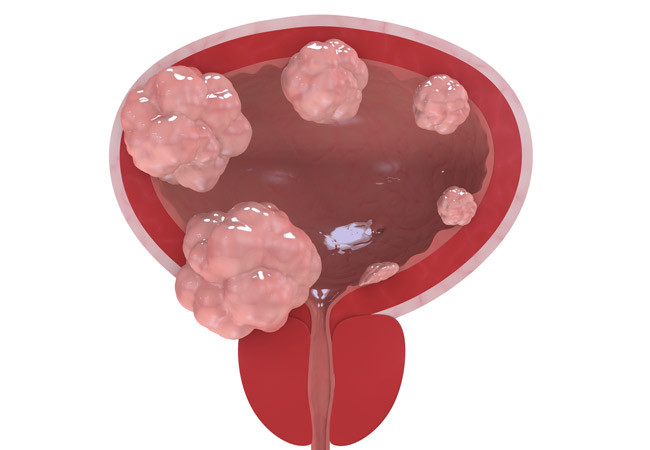

La uretromeatotomía es un procedimiento quirúrgico ambulatorio que se realiza para ampliar el meato uretral y el segmento distal de la uretra cuando existe una estrechez que dificulta la salida normal de la orina 🚻

Es una intervención frecuente en casos de estenosis del meato o estenosis uretral distal.

El urólogo puede recomendarla si presentas:

✔️ Chorro urinario fino o débil

✔️ Dificultad para iniciar la micción

✔️ Dolor o ardor al orinar

✔️ Desviación del chorro

✔️ Infecciones urinarias repetidas

Estos síntomas no deben normalizarse, ya que pueden progresar.